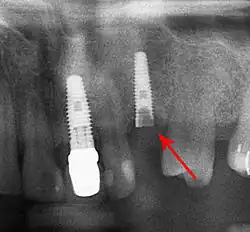

Bone loss (peri-implantitis) on implants over 7 years in a heavy smoker

Fracture of abutment screws (arrow) in 3 implants required removal of the remainder of the screw and replacement.